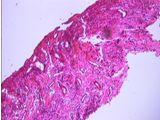

La histopatologia Nº 02-189, realizada en la Cátedra de Anatomía Patológica General y BMF de la Facultad de Odontología, informó que se trataba de epitelio malpighiano con francas hendiduras entre epitelio integro y el corion. El conjuntivo presentaba infiltrado inflamatorio moderado linfoplasmocitario con eosinófilos escasos e hiperplasia endotelial vascular (Foto 5)

Foto 5 Desprendimiento in toto del tejido conjuntivo y presencia de neovasos

“En suma: lesión erosiva ampollar cuya morfología orienta a penfigoide de las membranas mucosas”